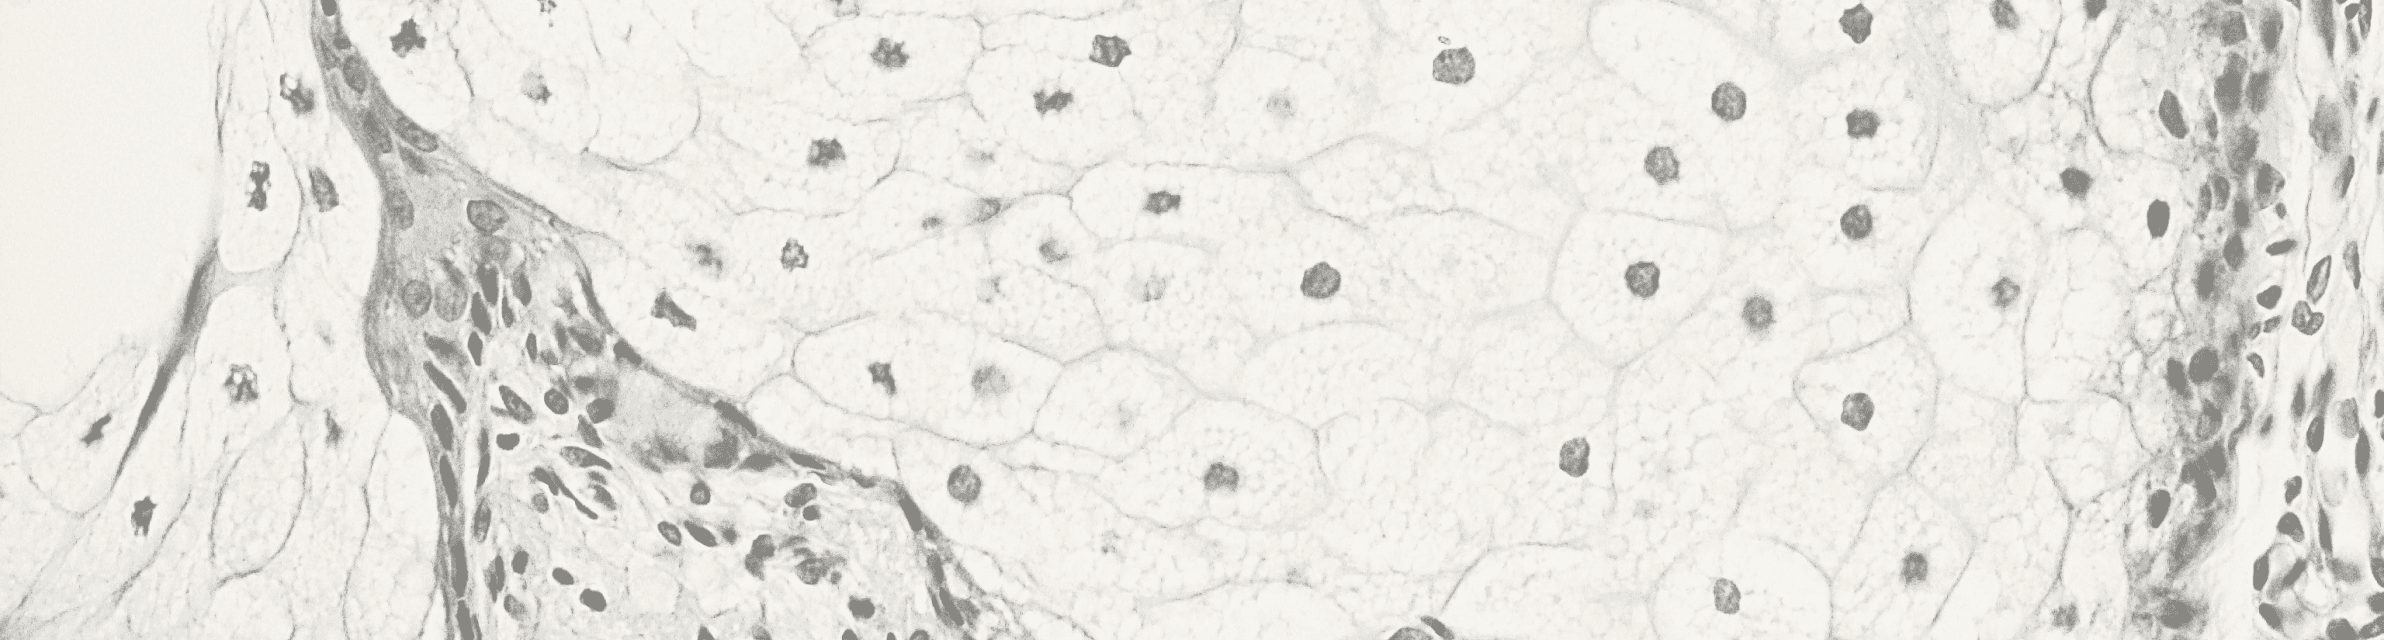

Enhancement of Intestinal Integrity

Bovine colostrum supplementation has been associated with improved intestinal barrier function. Studies have shown that it can reduce intestinal permeability, which is crucial for maintaining gut health and preventing the translocation of harmful substances.